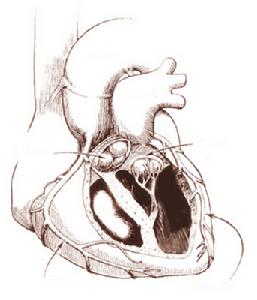

二尖瓣狹窄心臟圖單純二尖瓣狹窄時,左心室舒張末期壓力和容積正常。多數二尖瓣狹窄患者運動左心室射血分數升高,收縮末期容積減低。約有四分之一的二尖瓣狹窄嚴重者出現左心室功能障礙,表現為射血分數和其它收縮功能指數的降低,這可能是慢性前負荷減小的結果。多數二尖瓣狹窄的患者靜息心排血量在正常範圍,運動時心排血量的增加低於正常;少數嚴重狹窄者靜息心排血量低於正常,運動時心排血量不增加反而降低,其主要原因除了二尖瓣狹窄外,還有左右心室功能均已受損。此外,由於左心房擴大,難於維持正常的心電活動,故常發生心房顫動。心室率快的快速心房顫動可使肺毛細血管壓力上升,易加重肺淤血或誘發肺水腫。

早期,左心房處於代償時,由於二尖瓣狹窄,左心室舒張期,左心房血液進入左心室受阻,致使舒張末期仍有部分血液滯留於左心房內,加上肺靜脈來的血液,使左心房血液量比正常增多。此時,心肌纖維拉長以加強收縮力,心腔擴大以容納更多血液,導致左心房代償性擴張。因左心房負荷加重,心肌代謝增強,心肌纖維增粗,從而左心房代償性肥大,以維持相對正常的血液循環。後期,隨時間延長或病變加重,超過代償極限,左心房收縮力減弱而呈高度擴張(肌原性擴張),致左心房失代償。此時,左心房血液在舒張期不能充分排入左心室,引起左心房嚴重淤血,左心房壓力增高使肺靜脈血液進入左心房受阻,從而導致肺靜脈壓升高,隨即引起肺淤血。

由於肺靜脈壓升高及肺淤血,可通過神經反射引起肺內小動脈收縮,使肺動脈壓升高。長期肺動脈壓升高致使右心室代償性擴張、肥大。以後,右心室發生肌原性勞損,出現肌原性擴張。繼而出現右心室淤血。右心室高度擴張時,右心室瓣膜環隨之擴大,出現三尖瓣相對關閉不全,收縮期,右心室部分血液返流入右心房,加重了右心房負但,可致右心功能不全,引起體循環淤血。